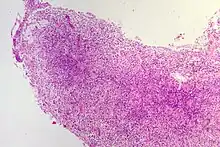

Le cholestéatome est une forme d'otite chronique avec présence d'épithélium pavimenteux stratifié dans l'oreille moyenne. Cet épithélium desquame et se kératinise (structure histologique de l'épiderme), et peut provoquer l'érosion voire la destruction des structures contenues dans et autour de l'oreille moyenne ( Histopathologie du cholestéatome)[1],[2].

Il se fait par visualisation du conduit auditif et du tympan (otoscopie). Il se manifeste par la présence d'une excroissance squameuse, le plus souvent à la partie postéro supérieure du tympan[7]. Le scanner crânien permet de visualiser l'extension et les éventuelles destructions osseuses.L'histopathologie post-opératoire est indispensable pour confirmer la nature de la lésion et celles qui lui sont associées.